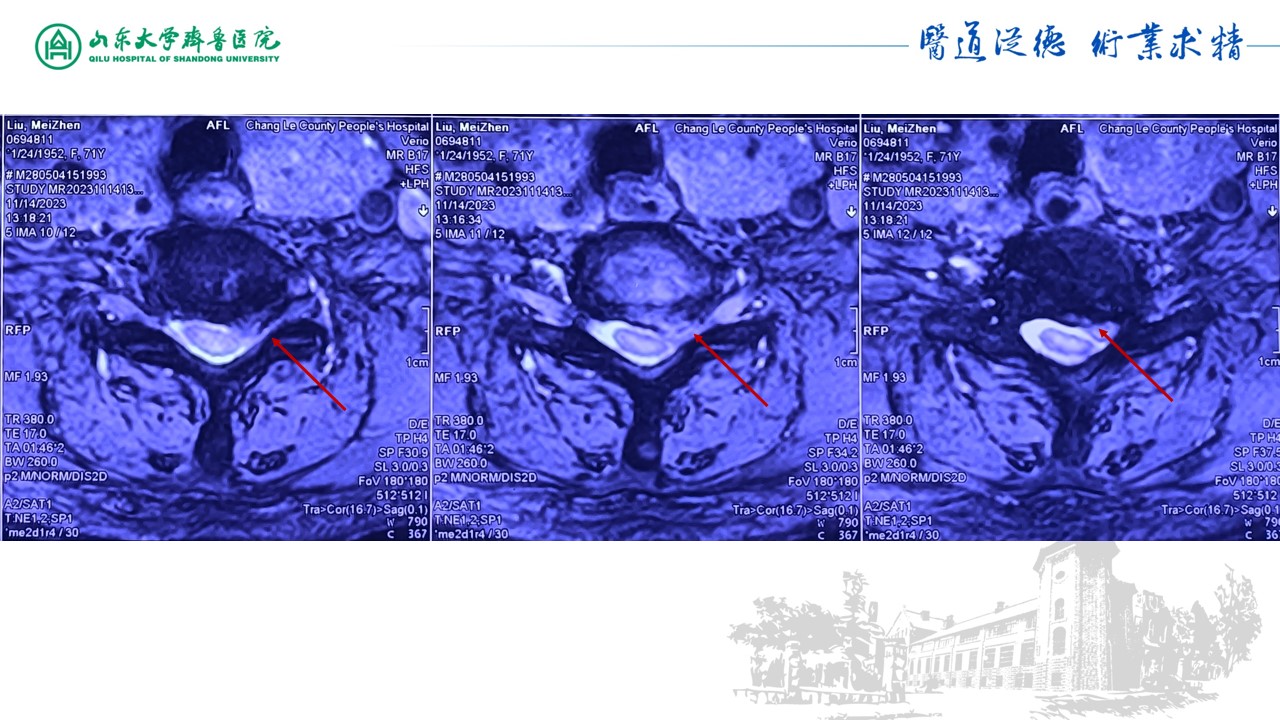

脊柱内镜下颈椎后路椎间孔减压髓核摘除术1例-山东大学齐鲁医院神经外科脊柱脊髓团队